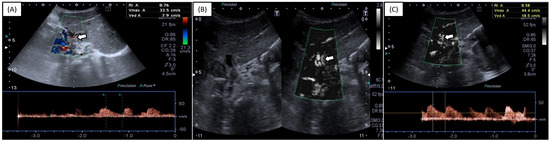

We describe a case of an asymptomatic 70-year-old female patient on whom a carotid ultrasound examination was performed that showed intima–media thickening and a 4 mm long carotid web with a 50% web-to-bulb ratio. Spectral Doppler waveform demonstrated a turbulent flow pattern and [...] Read more.

We describe a case of an asymptomatic 70-year-old female patient on whom a carotid ultrasound examination was performed that showed intima–media thickening and a 4 mm long carotid web with a 50% web-to-bulb ratio. Spectral Doppler waveform demonstrated a turbulent flow pattern and a peak systolic velocity increase of 100% (velocity ratio = 2) when compared with the common carotid artery. Therefore, the patient seemed to be at risk of stroke, and antiaggregant treatment was suggested. Full article